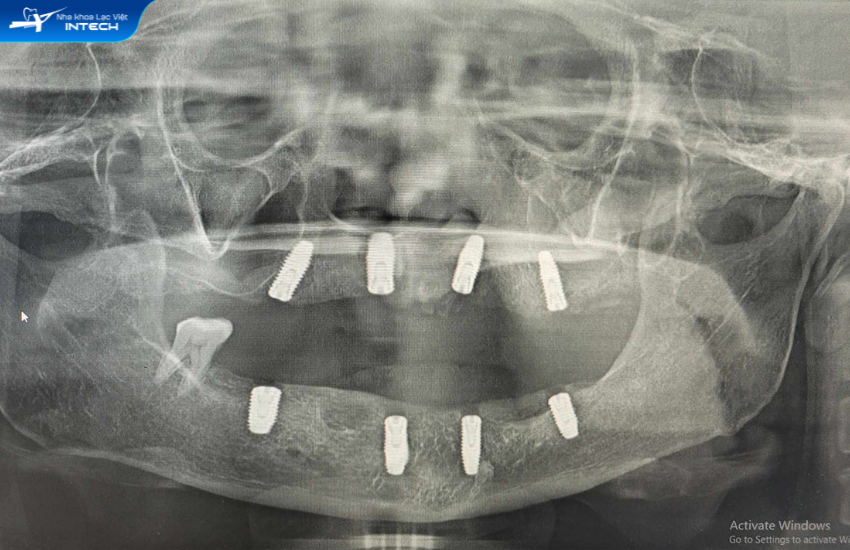

Điều trị chính cho cô Bộ là bác sĩ Nguyễn Hoàng Dương - Chuyên gia cấy ghép implant tại Lạc Việt Intech. Sau khi thăm khám và dựa trên kết quả chụp phim CT Conebeam, bác sĩ Nguyễn Hoàng Dương chẩn đoán về tình trạng răng của cô Bộ như sau:

• Mất răng toàn bộ hàm dưới

• Hàm trên còn lại vài răng bị lung lay không còn chức năng ăn nhai

• Chức năng ăn nhai suy giảm

Để khôi phục lại khả năng ăn nhai cũng như tính thẩm mỹ cho cô Trần Thị Bộ, bác sĩ đã đưa ra giải pháp trồng răng Implant All - On - 4 toàn hai hàm. Kỹ thuật trồng răng All - On - 4 được thực hiện bằng cách sử dụng 4 trụ Implant để nâng đỡ 12 chiếc răng trên cung hàm. Trong đó có 2 trụ Implant được cấy tại vị trí răng số 2 và 2 Implant cấy nghiêng một góc 45 độ tại vị trí răng số 5. Cùng với đó là sự hỗ trợ của Multi-unit Abutment có tác dụng liên kết trụ Implant và hàm giả cố định.

Sau gần 3 tháng chờ đợi chân răng Implant tích hợp với xương hàm, cuối cùng hôm nay cô Bộ cũng có được một hàm răng ưng ý vượt ngoài sự mong đợi khi khôi phục thành công 12 răng hàm trên và 12 răng hàm dưới. Giờ đây cô Bộ có thể ăn nhai một cách thoải mái mà không cần ninh nhừ như trước khi.